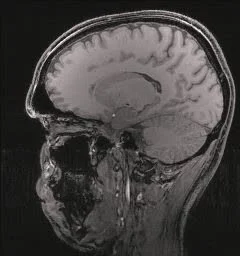

In healthcare, fluorescence helps doctors detect specific biomarkers associated with diseases, enabling early diagnosis and monitoring. For example, disease-causing forms of proteins can be detected by its binding to compounds that are brightly fluorescent under UV light.